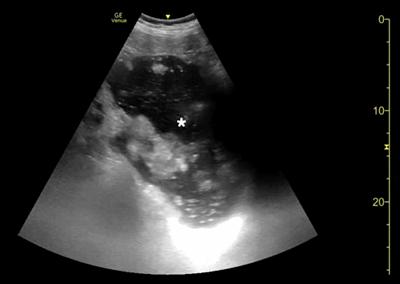

腹部床旁超声检查(POCUS)显示,胃部扩张并充满液体,高度疑似梗阻(图1,2)。

(图2)

随后患者进行紧急进行外科会诊评估。多次尝试放置鼻胃管,最终放置成功后引流非胆汁性胃内容物 2,000 ml,重复进行POCUS检查证实胃减压(图6)。

当怀疑有胃扭转时,选择初始的影像学检查非常重要,因为诊断延迟可能导致致命的并发症。CT检查高度可靠,主要有两种表现,即正常的胃窦幽门移行区和胃窦位置异常,诊断急性胃扭转的敏感性和特异性均为100%。POCUS是一种有效的非侵入性影像检查方式,主要用于床旁评估。此外,POCUS无辐射,并可根据临床情况随时进行重复检查。本例患者POCUS检查显示,胃部严重扩张,胃内容物分层,类似胃出口梗阻(GOO)的“黑白饼干”征象。POCUS还可以用来动态观察胃减压成功与否。